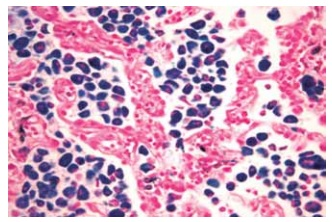

Foi solicitada uma tomografia, que demonstrou opacidades em vidro despolido com predomínio nas bases e periferia do parênquima pulmonar. Os exames laboratoriais não acusaram patógeno viral ou bacteriano, e o paciente foi submetido a um exame de biópsia pulmonar. A amostra cirúrgica foi recebida previamente fixada em formol tamponado a 4% e submetida ao processamento da análise com inclusão total do material. As secções obtidas foram coradas utilizando hematoxilina e eosina.

Legenda: Espessamento de septos com infiltrado inflamatório.